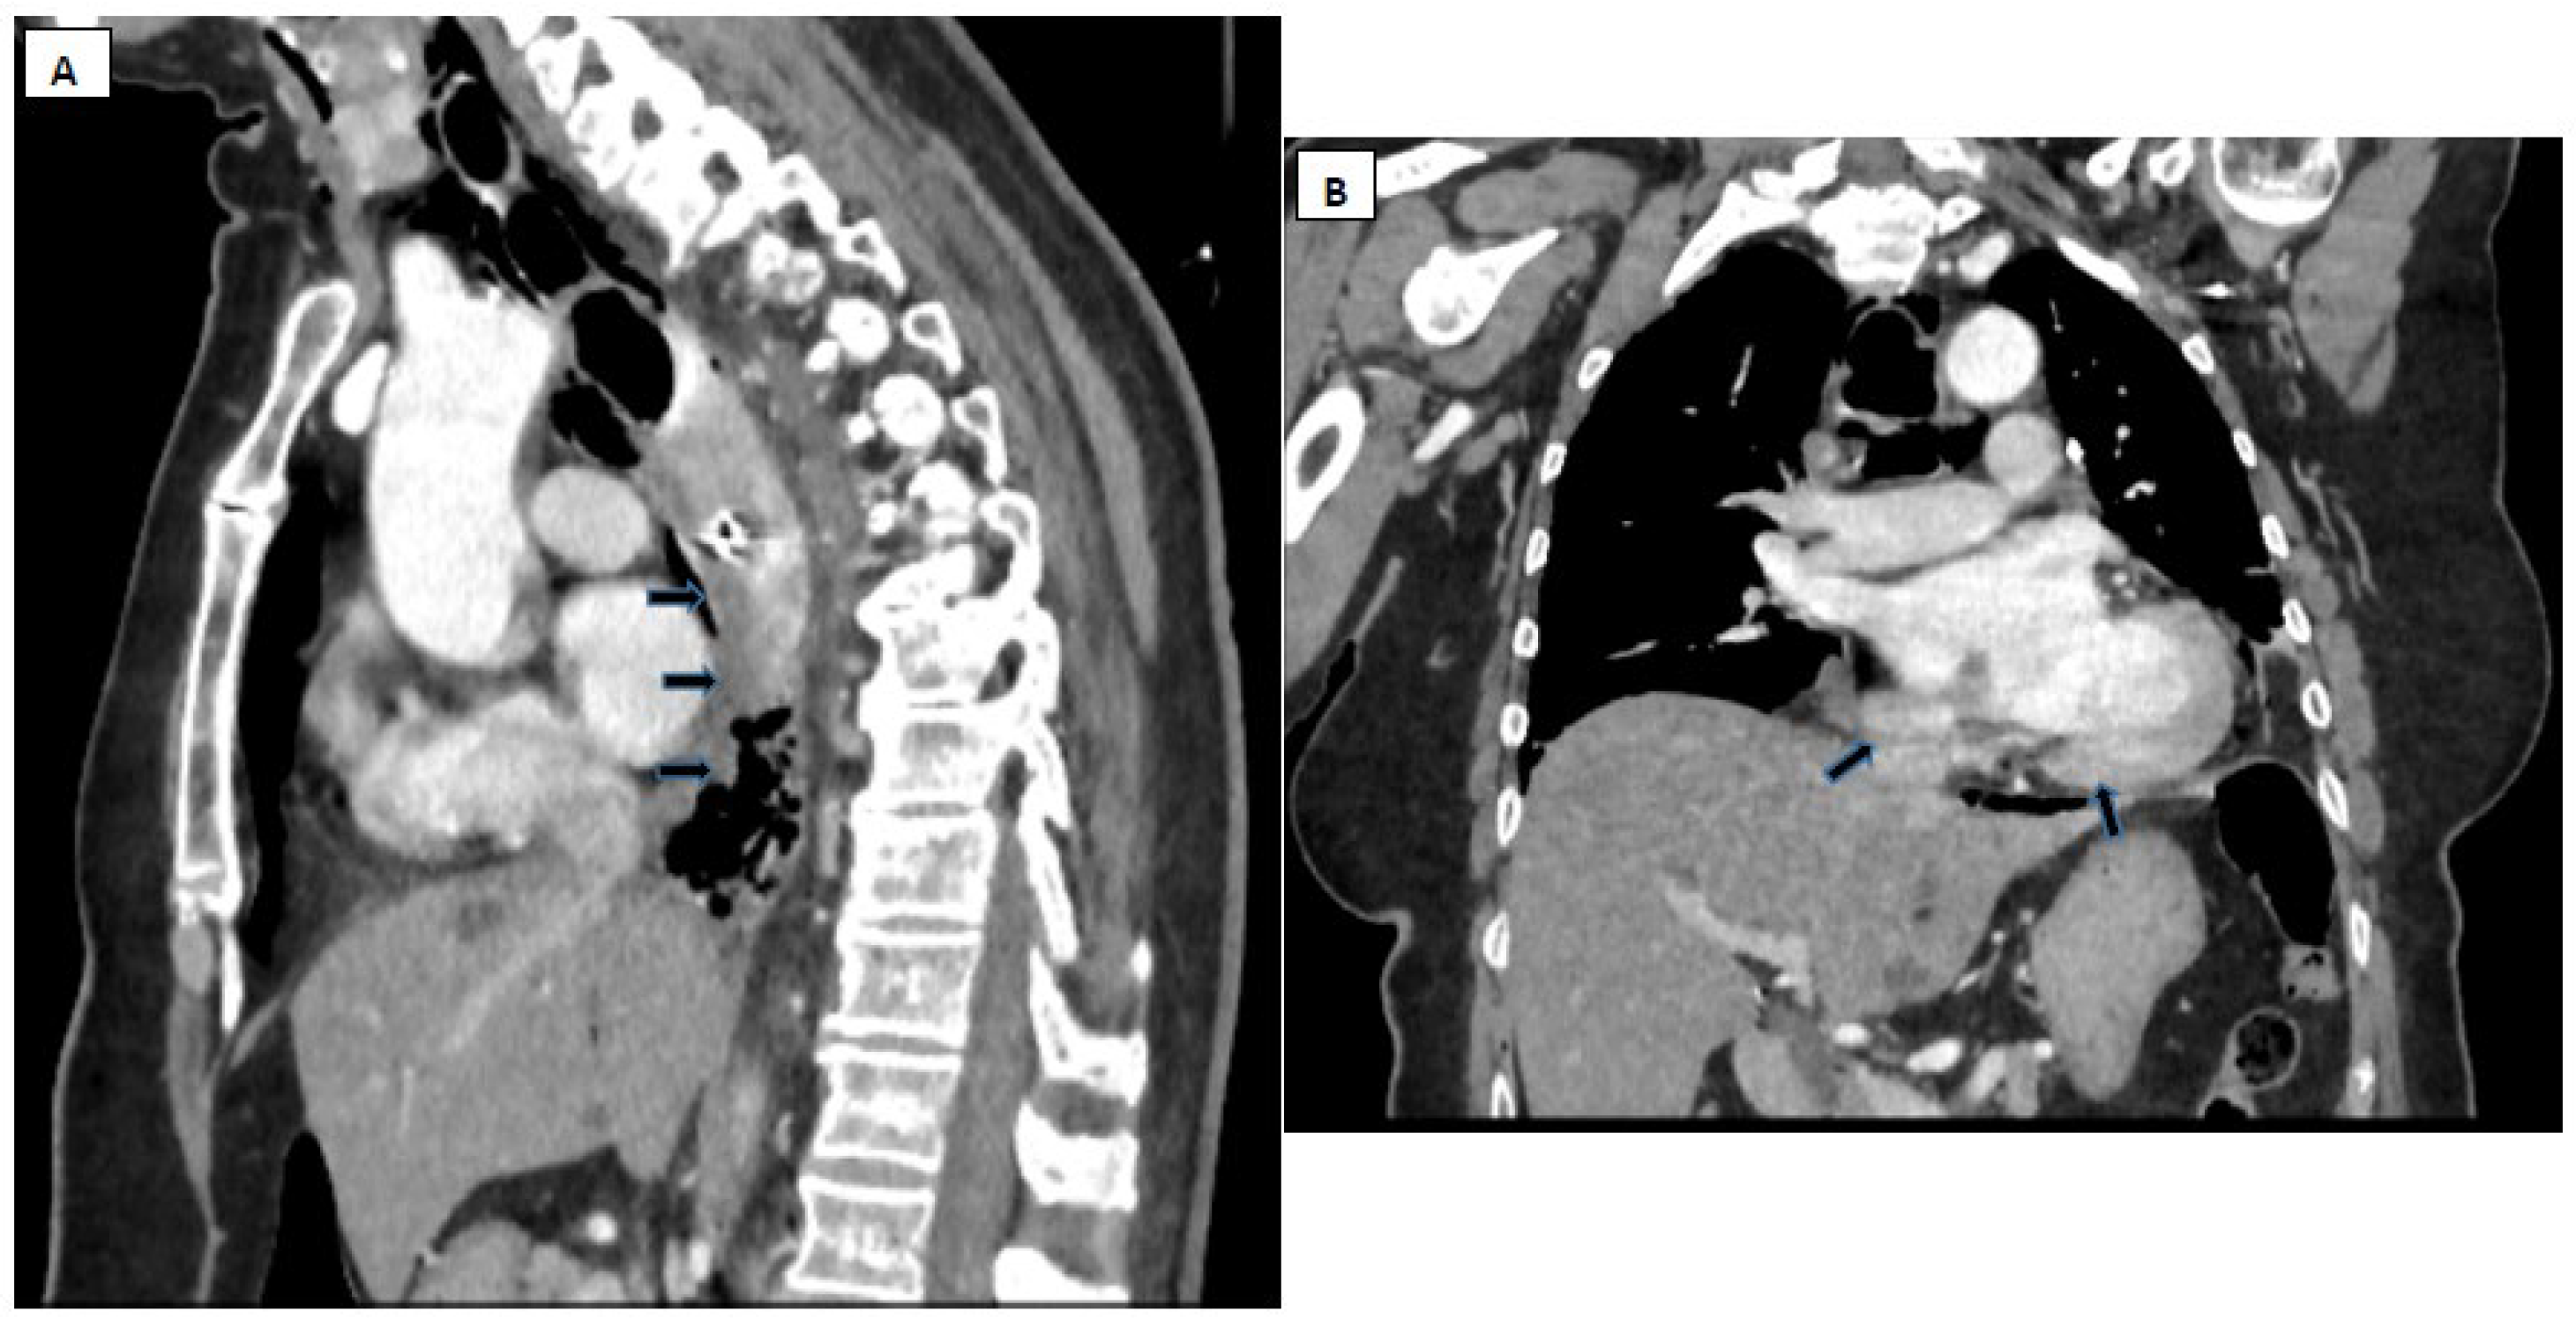

- Pneumomediastinum

- Localized periaortic gas

- Mediastinal fluid collections

- Thickened esophageal wall

- Gas within thoracic soft tissues, neck, or around major vessels

- Pneumoperitoneum

- Gas in the retroperitoneal space

- Oral contrast extravasation from the esophageal lumen [10].